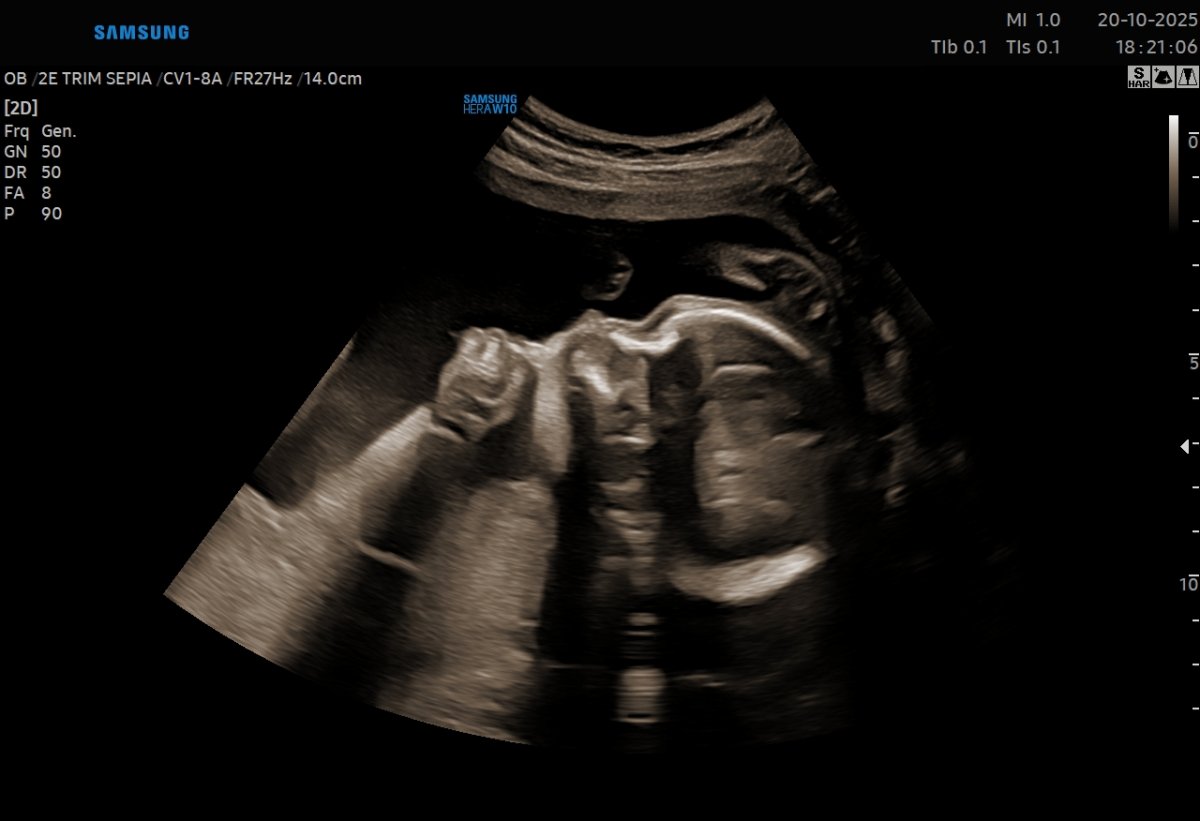

Gallerie de photos